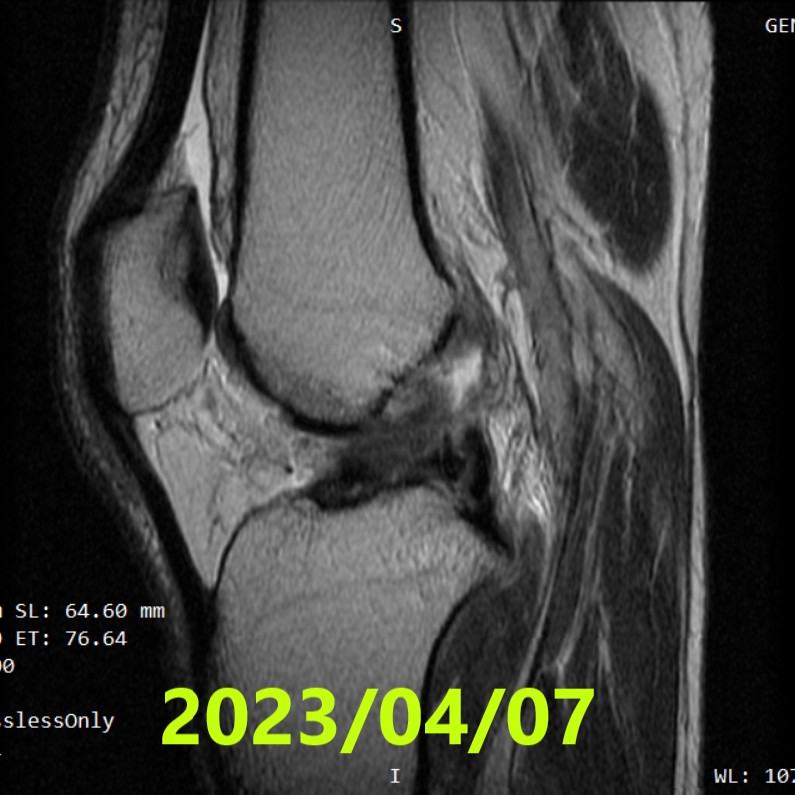

Valutazione iniziale(RM #1)

- Data: 7 aprile 2023

- Diagnosi: rottura completa del LCA del ginocchio destro

- Lettura indipendente (3 radiologi): concorde classificazione di Ihara IV(monconi indistinti / morfologia scadente)

- RM #1(07/04/2023): Ihara IV(concorde, 3/3 lettori)